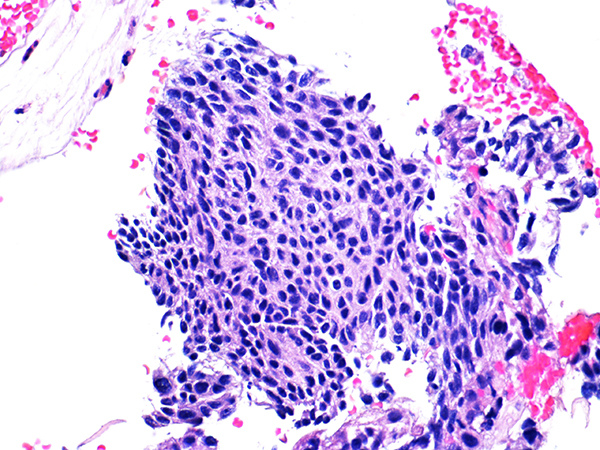

![]() Case 2

Soft Bx CIN 2

40x - High Power